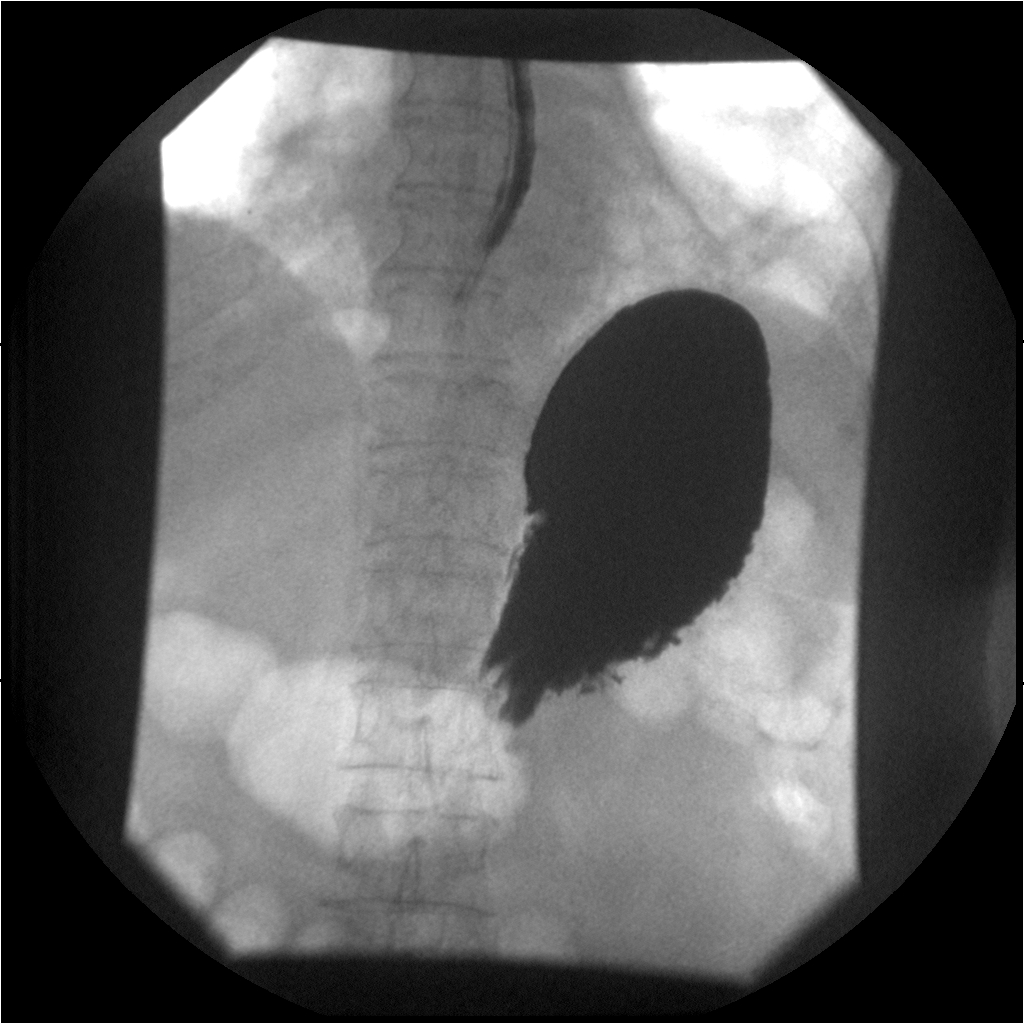

What is the radiographic appearance of infiltrative gastric carcinoma?

Thickened walls, narrowed lumen, rigid non-contracting 'fixed stomach', loss of rugal folds.

What is the hourglass stomach?

Circumferential involvement causing mid-gastric narrowing.

What is the radiographic appearance of proliferative type of gastric carcinoma?

Polypoid mass projecting into the lumen; may mimic ulcer.

What are the best imaging studies for gastric carcinoma?

UGI for detection; CT for staging, treatment, and follow-up.